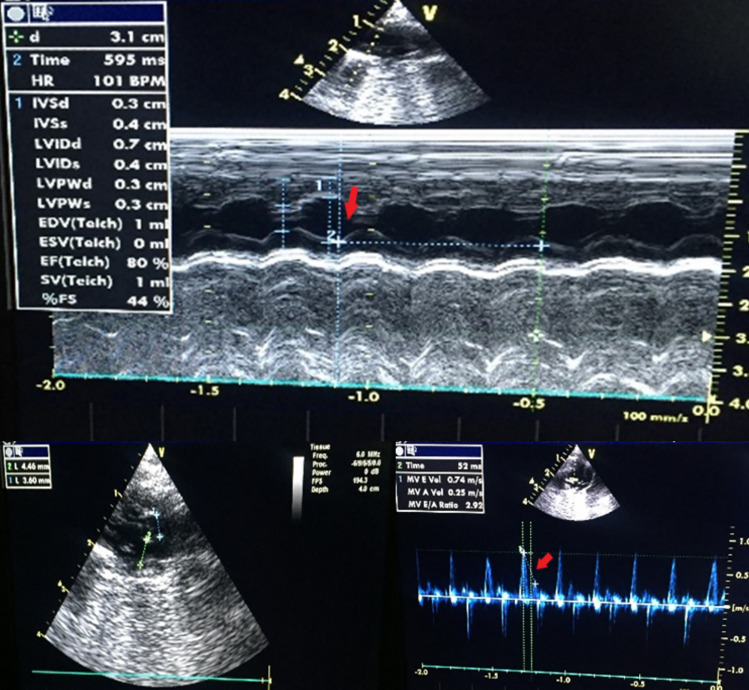

Methods: Wistar albino rats were divided into five groups: control, acute low-dose (ALD, 0.5 mg/kg), acute high-dose (AHD, 5 mg/kg), subacute low-dose (SALD, 0.5 mg/kg for 14 days), and subacute high-dose (SAHD, 5 mg/kg for 14 days). Cardiovascular effects were assessed using echocardiography, hemodynamic and ECG analysis, histopathology, biochemical markers, and LC-MS/MS quantification of JWH-018 and its metabolites in heart tissue.

Results: Acute high-dose JWH-018 caused bradycardia and hypotension, while subacute high-dose increased heart rate but continued to lower blood pressure. JWH-018 induced cardiac arrhythmias, conduction blocks, and ischemic ECG changes, with prolonged QT intervals in subacute high-dose rats. Histopathological findings revealed myocardial infarction-like features, including contraction bands and ischemic damage, particularly in subacute groups. Elevated pro-BNP and triglycerides indicated cardiac stress and metabolic effects. JWH-018 and its metabolites were detected in heart tissue, primarily in high-dose groups.